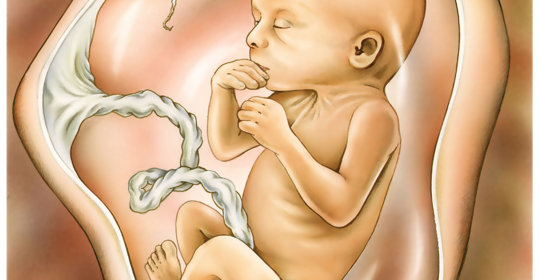

正弦胎心率:孕期小百科,詳細瞭解胎心率異常與預防!

胎兒水腫:孕期健康提醒,關愛寶寶發育的每一步!

胎勢異常:關注胎兒健康,瞭解胎兒體位問題及調理!

胎心不規則:孕期安全須知,提前瞭解及時防範!

胎兒發育遲緩:瞭解問題,關注孕期,科學保護胎兒!